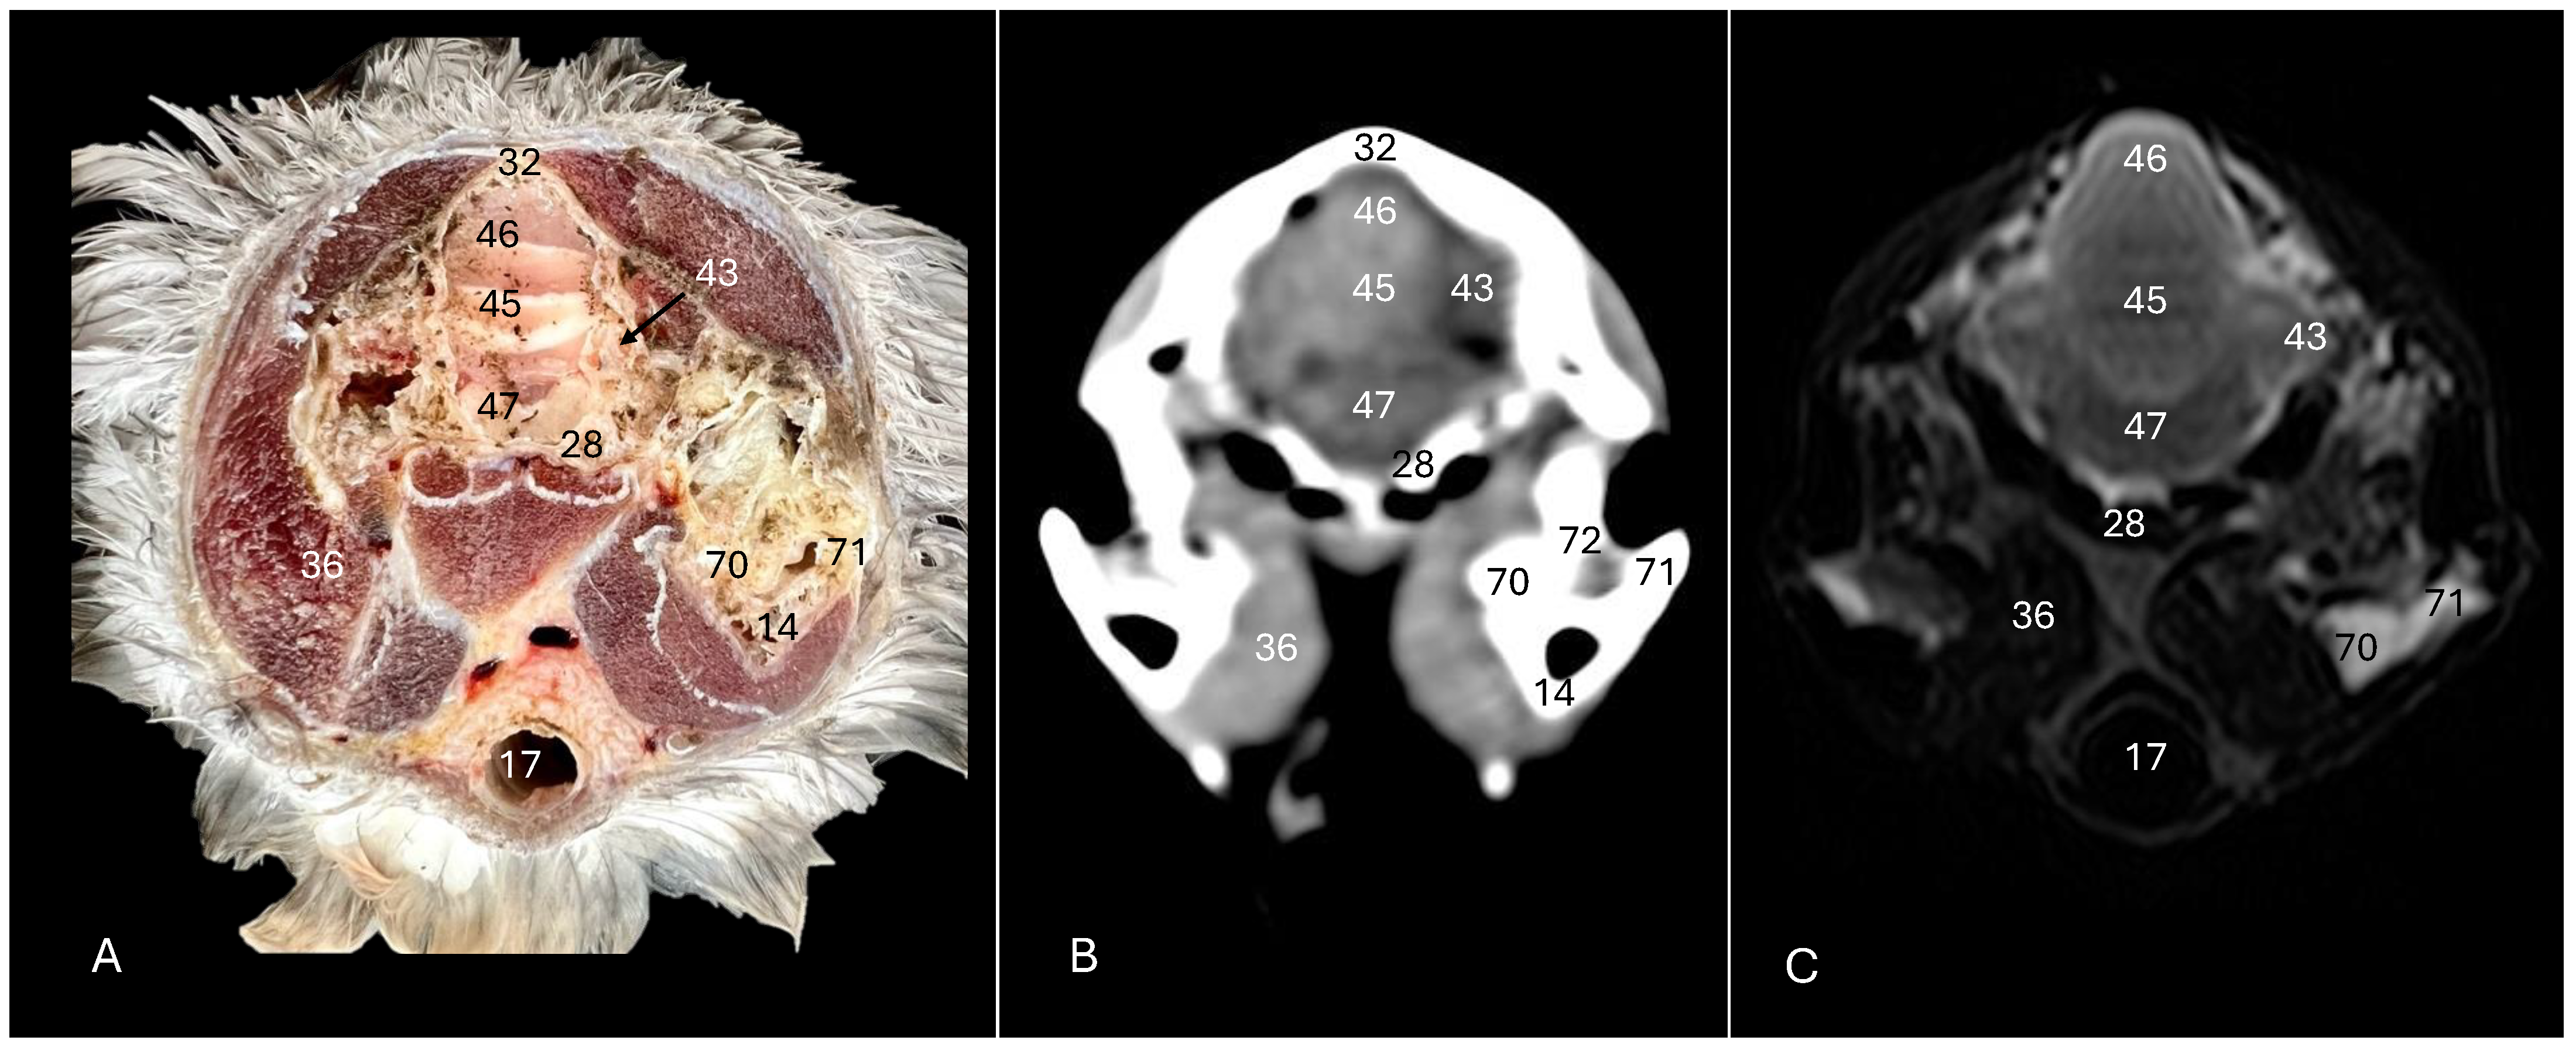

Cory’s Shearwater (Calonectris borealis): Exploring Normal Head Anatomy through Cross-Sectional Anatomy, Computed Tomography and Magnetic Resonance Imaging

3. Result

3.1. Anatomical Sections

3.2. Computed Tomography (CT)

3.3. Magnetic Resonance Imaging (MRI)